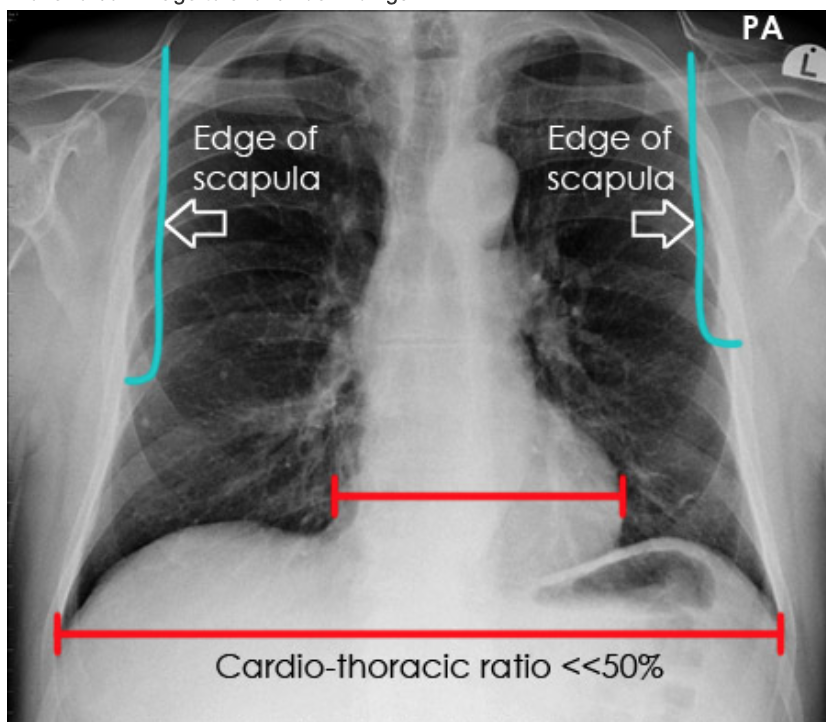

AP or PA

PA = scapular further lateral